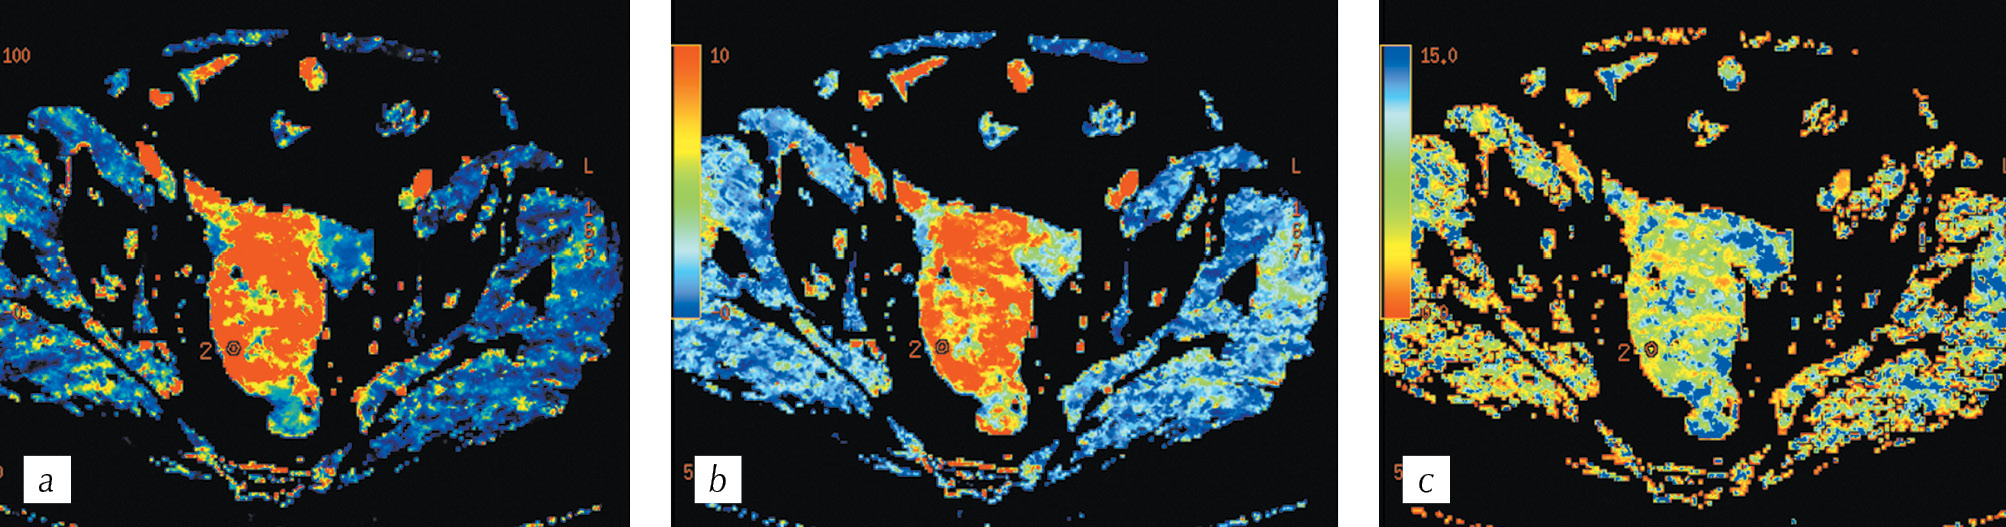

It was revealed that for a moderately differentiated adenocarcinoma, the visual assessment of the parametric cards is characterized by a clear difference between the tumor vascularization and the adjacent intact intestinal walls. Further, the boundaries of infiltrative changes in the intestinal wall during PCT were wider when compared to that obtained during standard spiral CT (Fig. 7, a, b). Following the placement of the ROI 2 labels in the tumor, and ROI 3 labels in the wall of the intact intestine, we obtained tables of digital values that demonstrate clear differences in the blood flow velocity indicator as BF in the tumor wall minand intact intestine was 112 ml/100g per min and 16 ml/100 g per min, respectively (Fig. 8, a). The density–time plot indicates functional changes in the tumor tissue in the form of the rise in curve 2 after 15 s of scanning, with a peak at 28 s and 3 s after the appearance of a peak in the afferent vessel. The green curve indicate that changes in the intact intestinal wall had a relatively straight course without significant peaks (Fig. 8, b).

Fig. 7. HCT, multiplanar reconstruction in the axial plane in the portal phase (a) and СT perfusion, parametric map of the blood flow (b) with ROI 2 in the invasive part of the tumor and ROI 3 in the intact intestinal walls

Рис. 7. Спиральная компьютерная томография, мультипланарная реконструкция в аксиальной плоскости в портальную фазу сканирования (a) и перфузионная компьютерная томография, цветная параметрическая карта скорости кровотока (b) с метками ROI 2 в инвазивной части опухоли и ROI 3 в смежных интактных стенках кишки

Fig. 8. Summary tables of perfusion parameters (а), the density-time graph (b) for the ROI 2 area in the tumor and ROI 3 in the intact intestinal wall

Рис. 8. Сводные таблицы числовых значений (a), график «плотность – время» (b) для меток ROI 2 в опухоли и ROI 3 в интактной стенке кишки